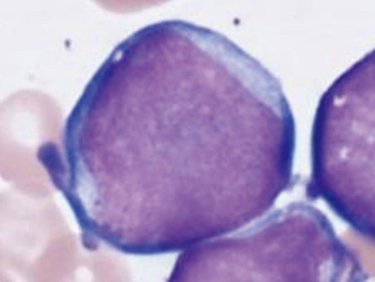

骨髄芽球